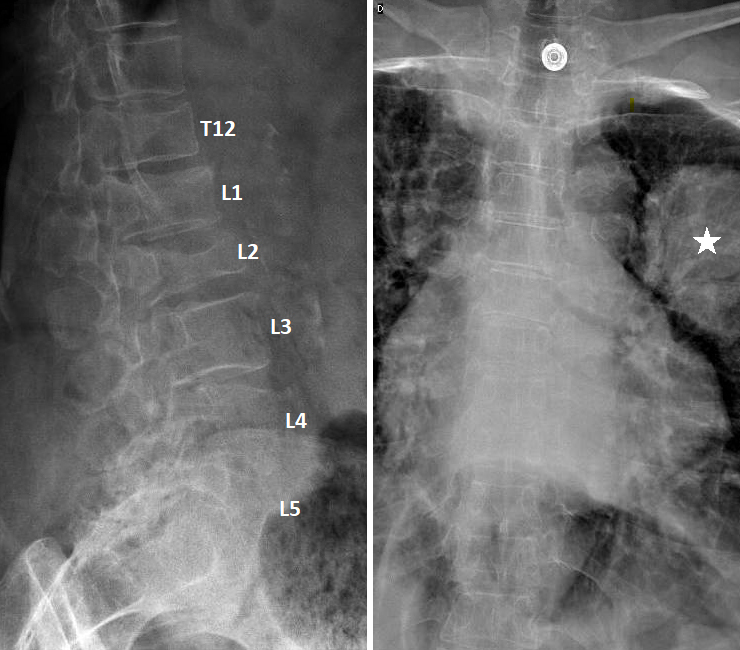

Vous faites réaliser une radiographie du rachis dorso-lombaire dont voici les clichés. Figure 1 (Salomé Abdellaoui, La Revue du Praticien)

Question 4 - Qu’identifiez-vous sur cette radiographie (une ou plusieurs réponses exactes) ?

Il existe bien une image pulmonaire suspecte mais elle est située dans le poumon gauche (légendée par une étoile).

Il s’agit d’une électrode d’électrocardiogramme.

On observe sur les radiographies une fracture vertébrale de L2, qui n'a pas de caractère évident de malignité (voir la suite du dossier), ainsi que des fractures plateaux supérieurs des vertèbres T12 et L1. Figure 2 (Salomé Abdellaoui, La Revue du Praticien)